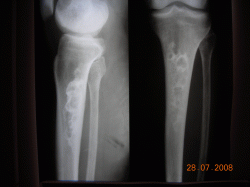

Здравствуйте коллеги. Я молодой врач рентгенолог, работаю первый год, после интернатуры, единственным рентгенологом в ЦРБ. Выскажите, пожалуйста, свое мнение по данному случаю.

Пациент, мужчина 50 лет, находился на обследовании и лечении в обл. центре по поводу ревматоидного артрозо-артрита правого голеностопного с-ва. Произведены сравнительные рентгенограммы обоих голеностопных суставов и случайно выявлены изменения в костях левой голени. Со стороны левой нижней конечности никаких жалоб не предъявляет. В выписке описания снимков нет, заключение: "Деформирующая остеодистрофия?"

Какой патологии, по вашему мнению, могут соответствовать изменеия в левой б/берцовой кости, аналогичная картина в н/трети левого бедра.

Позволю себе не согласиться с мнением уважаемого коллеги. На представленных рентгенограммах фрагментов левой голени (верхней и нижней 1/2) в проксимальном и дистальном метадиафизах б/берцовой кости отмечаются эксцентрично расположенные, ориентированные вдоль кости участки деструкции костной ткани неоднородной ячеистой структуры, достаточно четко отграниченные от окружающей ткани склеротическим ободком, слегка деформирующие (едва заметно вздувающие) кость на уровне поражения. Кортикальный слой сохранен, периостальной реакции, гиперостозов нет. Эта картина соответствует фиброзной дисплазии. Мелореостоз характеризуется чаще всего практически однородным, "стелющимся" эксцентрично вдоль длинной оси кости склерозом в виде слегка волнистой полосы, переходящим через линию суставов на другие кости. Корковый слой изменяется всегда, утолщаясь при этом как в сторону к/м канала (эндостально), так и наружу (периостально). При этом поверхность кости приобретает волнистые, местами гребневидные "оплывающие" контуры (стекающая свеча). Склертические полосы могут быть прерывистыми и расслоенными, но ячеистый рисунок для этого процесса не характерен.

Искала мелореостоз, наткнулась на эту ветку... Должна разочаровать, Валентин Львович, здесь обызвествленные интрамедулярные инфаркты, а не мелореостоз

Конечно, инфаркты, другого не дано.